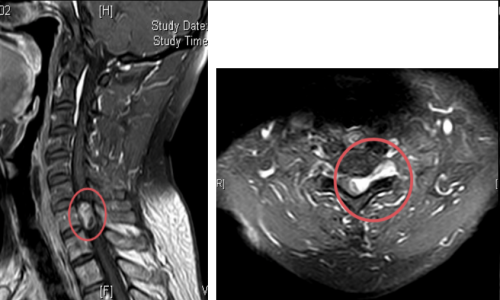

术前核磁检查颈胸段椎管内存在占位性病变,且脊髓已被挤压成线形